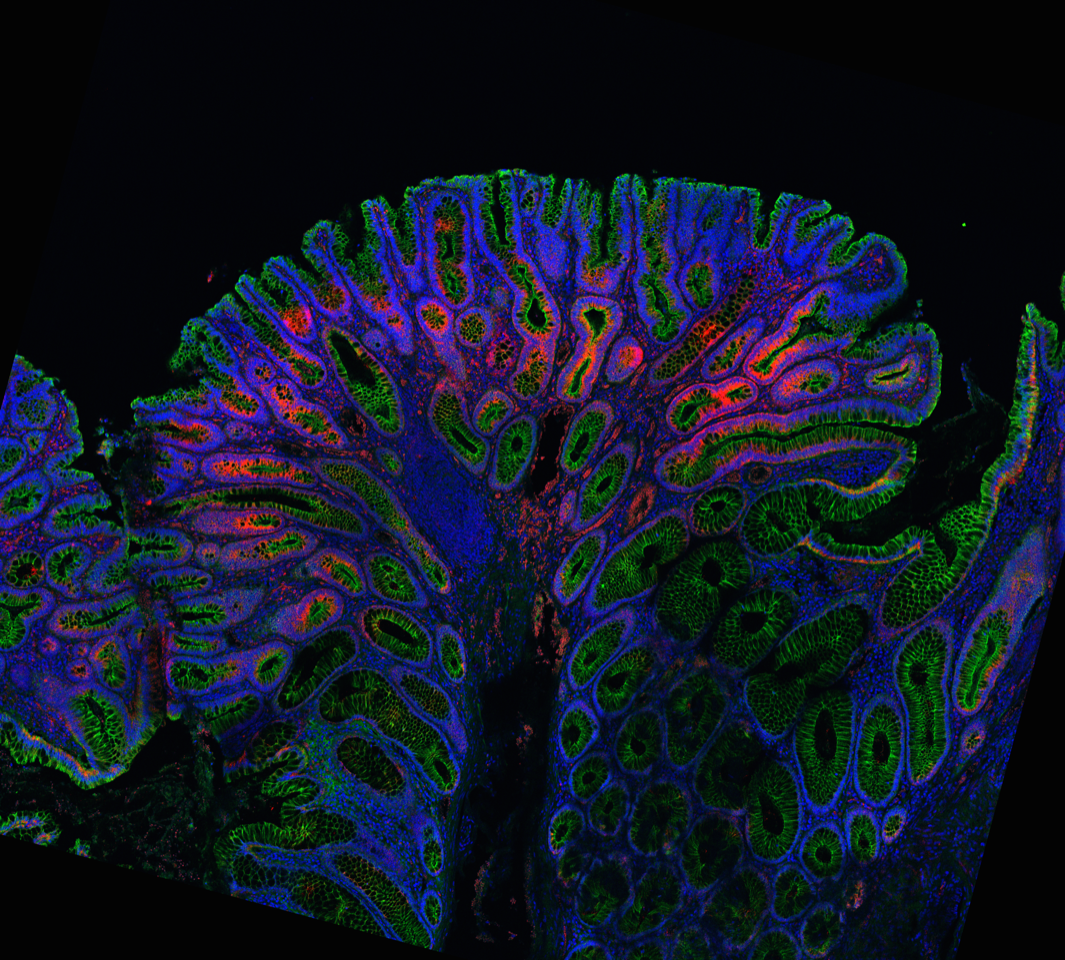

Stem cells in the gut are located in the so-called crypts and are responsible for the formation of different cell types that are necessary for the renewal of the gut lining. This process is essential for a healthy gut. “During this process, spontaneous mutations can arise, for example in the APC gene,” says Oncode Investigator Louis Vermeulen. “These mutations can cause polyps to form in the gut, a precursor to colon cancer.”

When a stem cell acquires an APC mutation, competition arises between the healthy and mutant stem cells in a crypt. Researchers at the Vermeulen lab have now shown for the first time that these cells are in so-called 'super-competition' with each other. “Using organoid technology, we discovered that mutant cells actively suppress the growth of healthy cells,” first author Sanne van Neerven explains. “We then investigated whether we could suppress this negative effect. It turned out that we could boost the healthy cells by treating them with lithium. This resulted in fewer polyps, which in turn reduces the risk of developing colon cancer.”